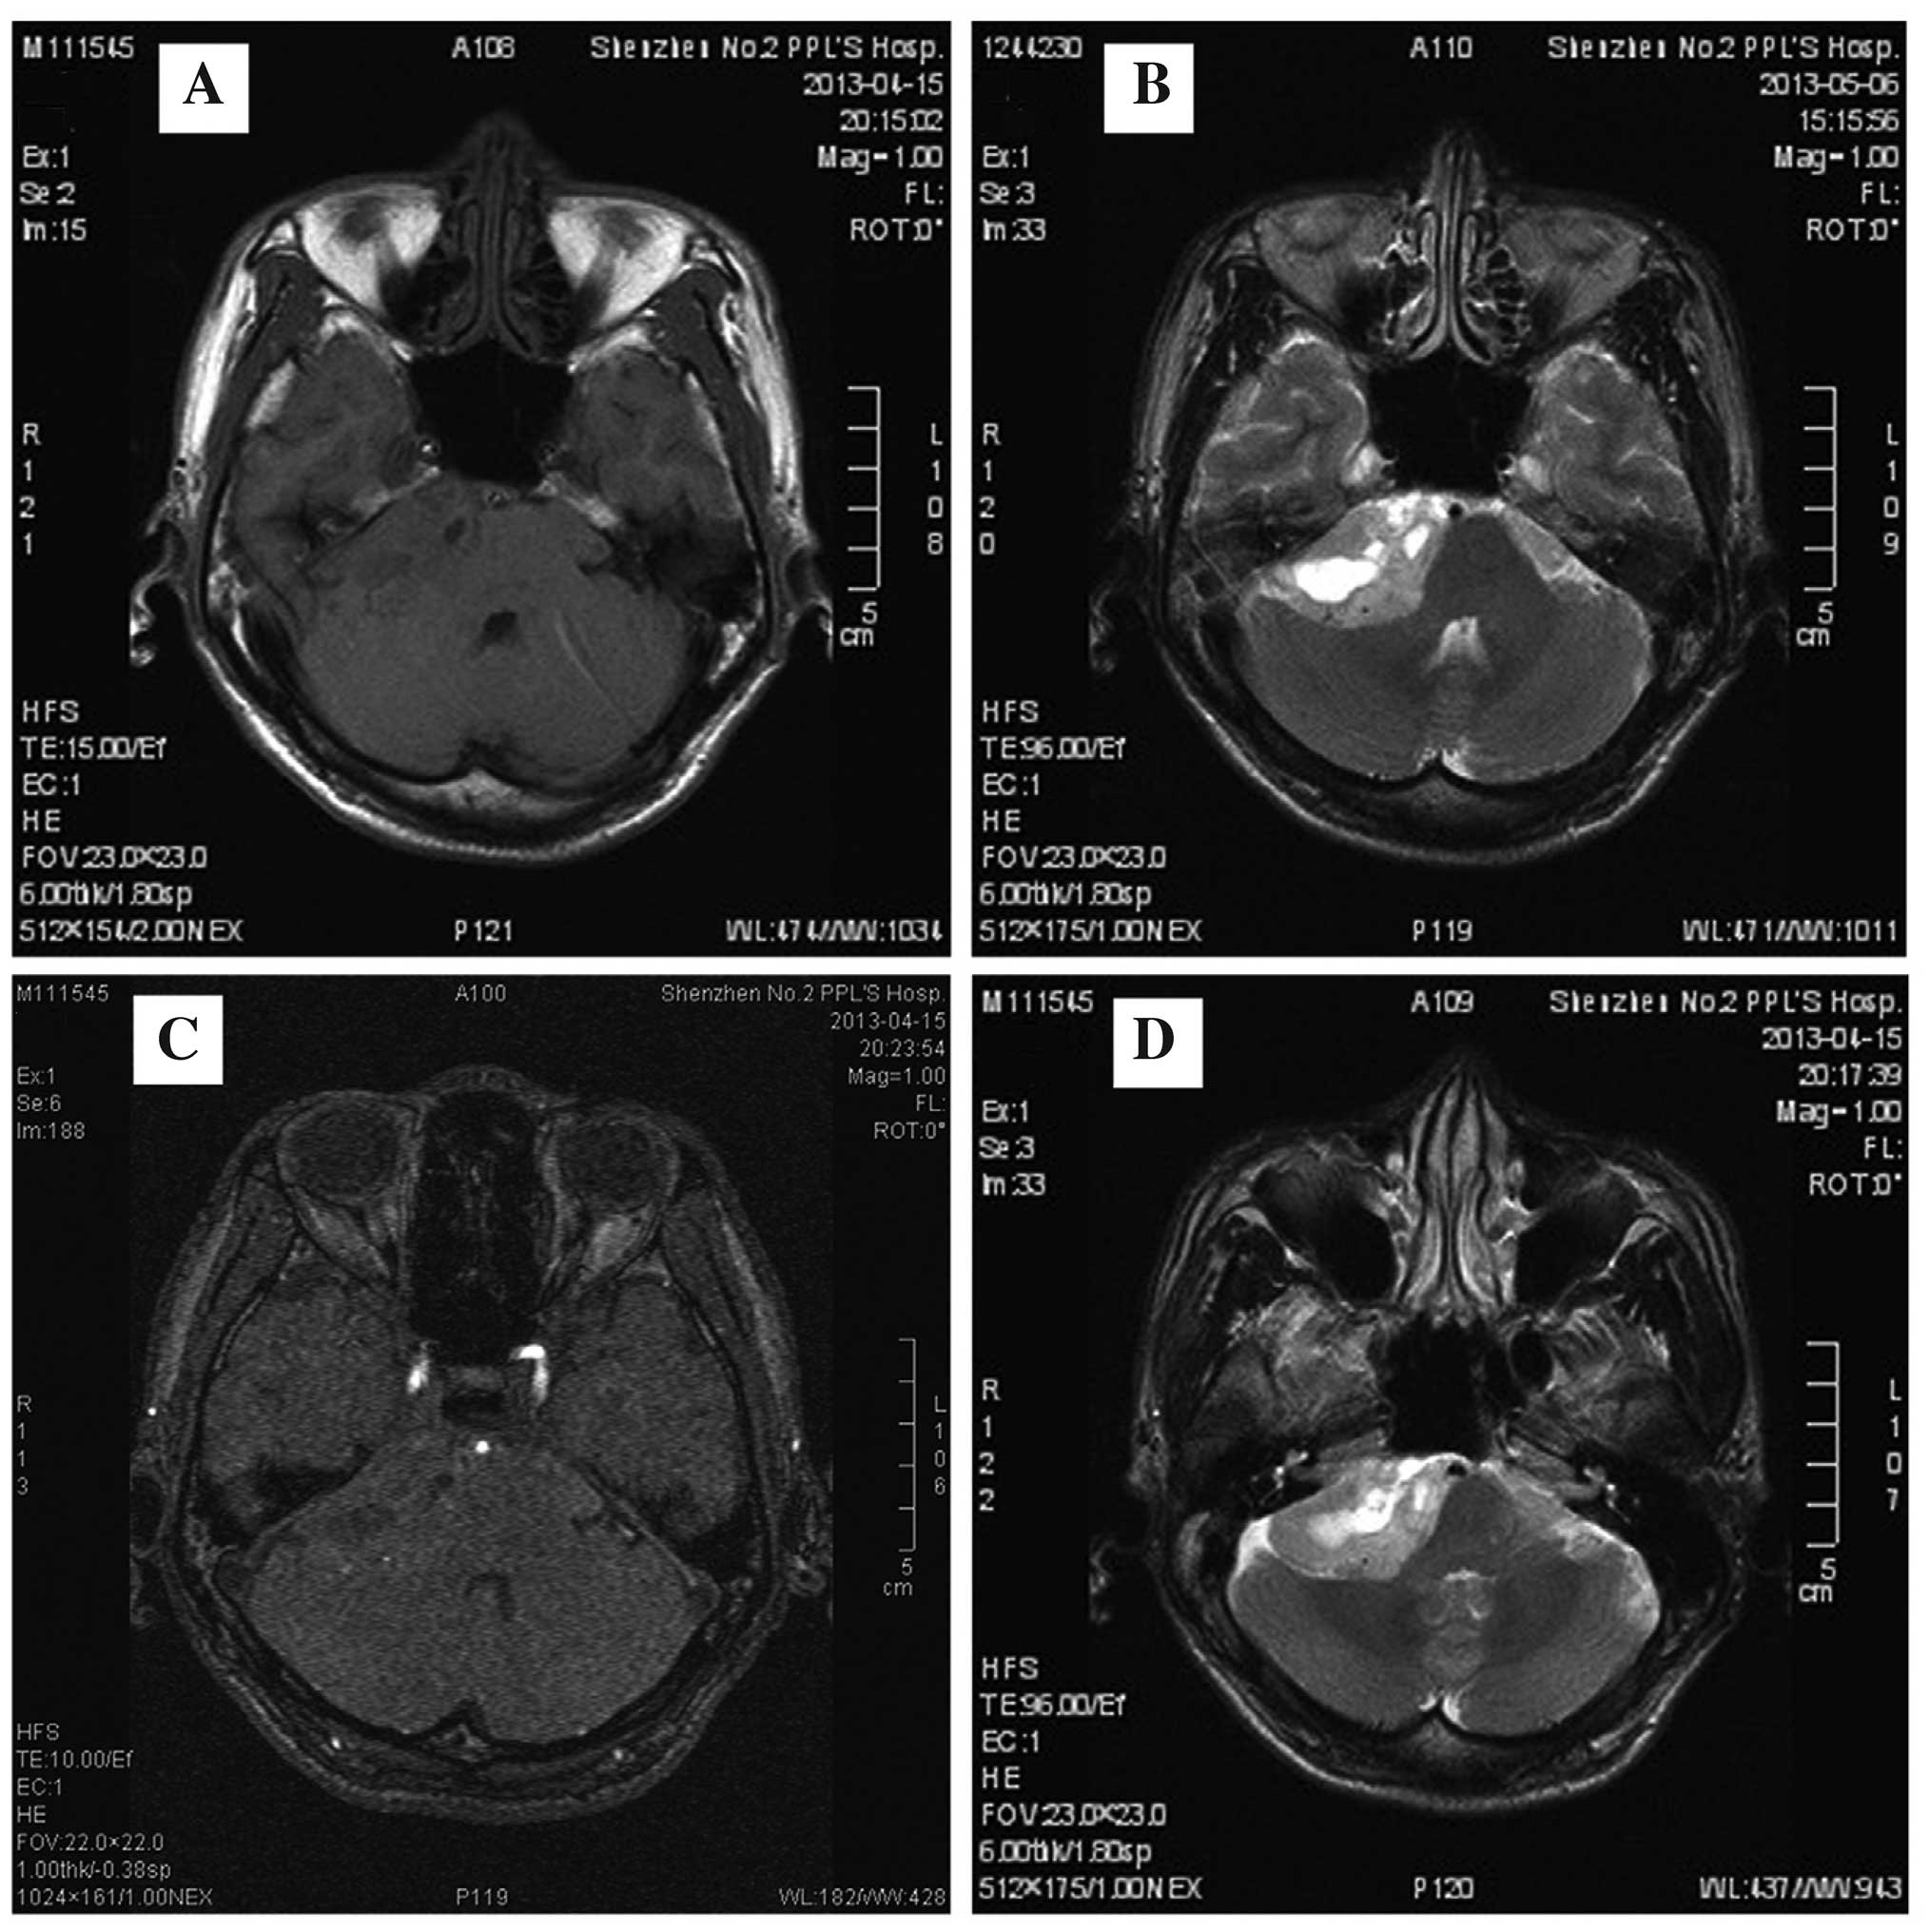

MRI provides excellent assessment of the IAC and the bony changes occurring in the canal walls, and it provides excellent demonstration of the content of the canal. patient might generate a single dictation on the part of the radiologist. found 2.5 mm mass in right internal canal consistent with acoustic neuroma. (With permis- sion from Kasper DL, Braunwal E, Fauci A, et al. Another example is the encoding of clinical observations using LOINC codes. To avoid having acoustic trauma, people should wear protective ear plugs or ear-cover protectors to minimize damage to their ears when using loud equipment.Įveryone should be aware of risks of acoustic traumas that are connected with such activities as shooting guns, using chain saws, lawn mowers, driving motorcycles, or when using snowmobiles.Īnother way of avoiding acoustic trauma is to refrain from listening to loud music for long periods of time.Īcoustic trauma can occur as a result of an individual's occupation, such as rock musicians, construction workers, airline ground crew members, or by using earphones and headphones, etc. Enlargement of the Internal Auditory Canal and Associated Posterior Fossa Anomalies in PHACES Association. Magnetic resonance imaging (MRI) is presently the study of choice for assessment of the internal auditory canal (IAC). Sagittal MRI of the brain in spinocerebellar ataxia.